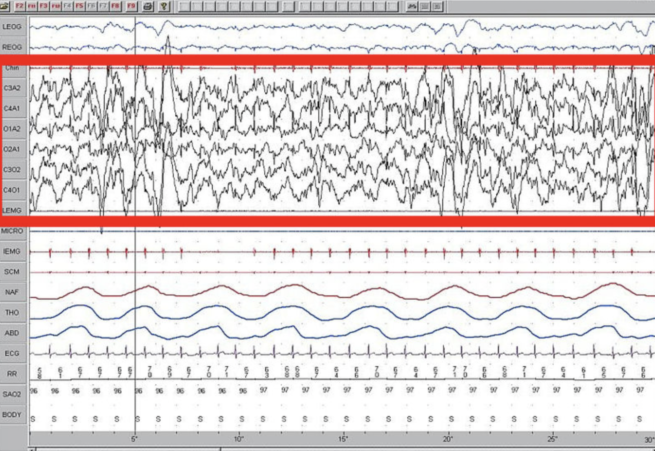

Sleep and Breathing

Sleep Medicine

Sleep Science